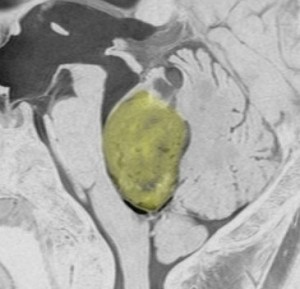

第4脳室とは

後頭部に近い所にあります。黄色が第4脳室で,髄液の通り道(出口)です。

前方には脳幹部,後ろは小脳虫部です 。

上は細い中脳水道につながって,下はマジャンディー孔と左右のルシュカ孔に開いています。